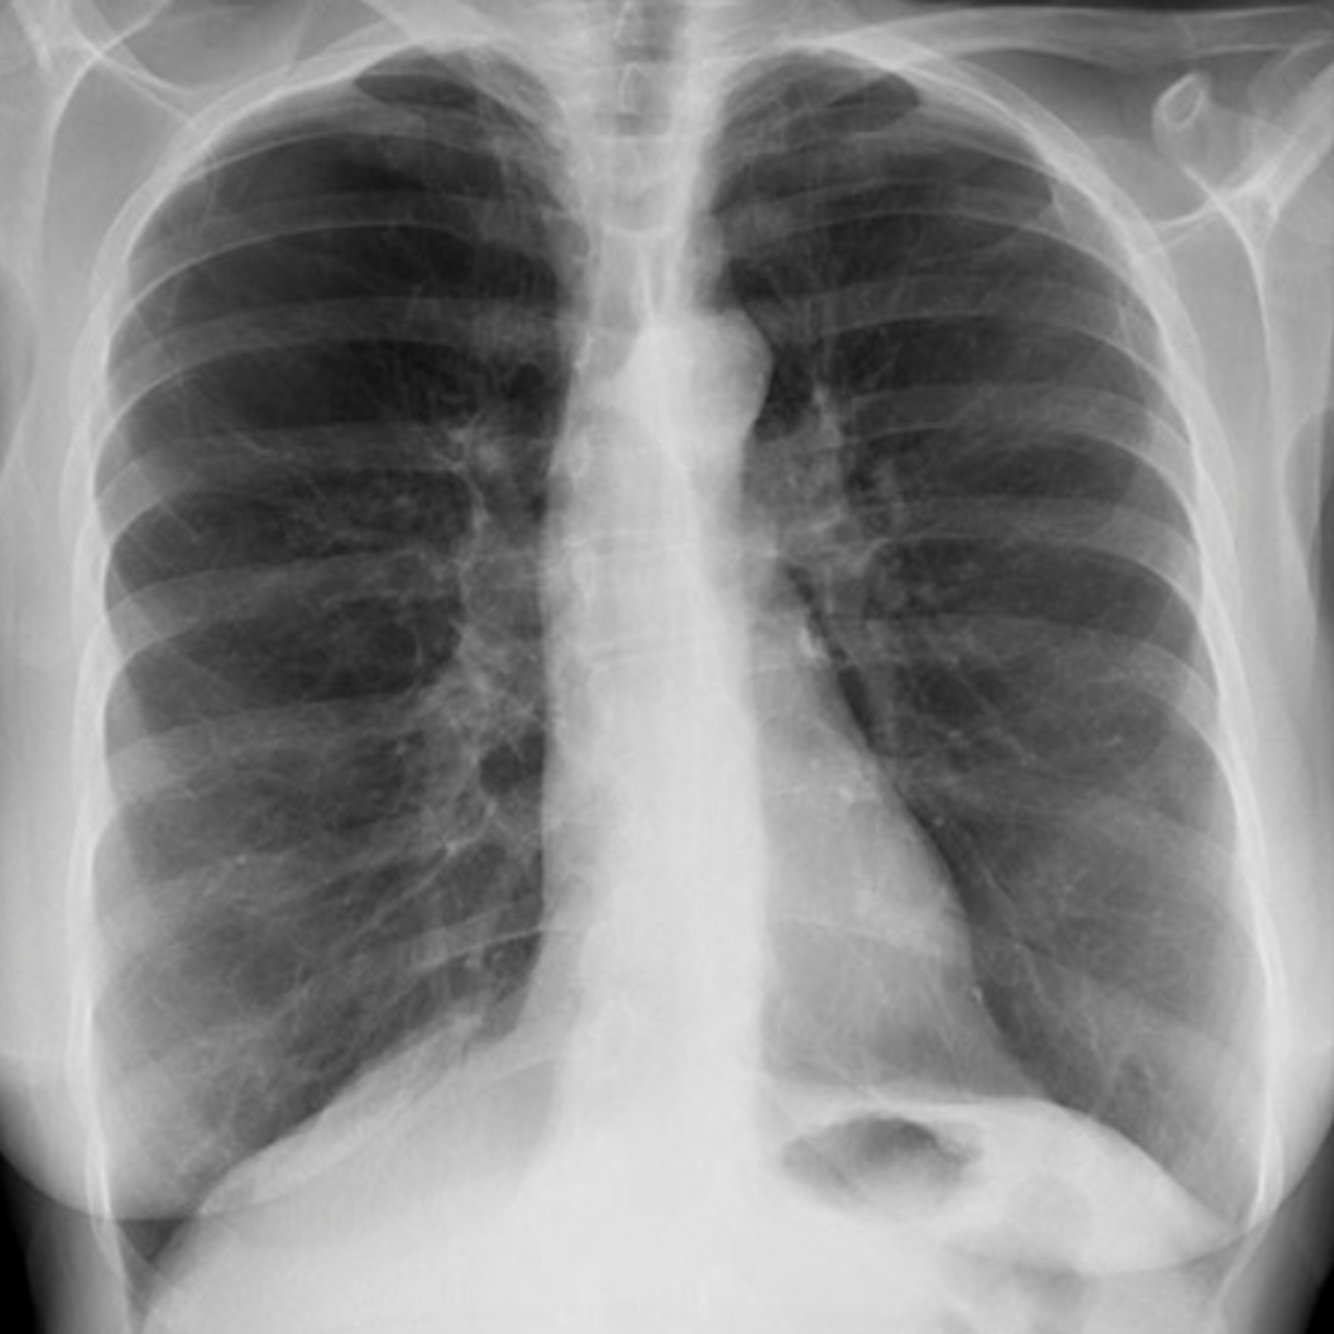

A 67 year old man is scheduled for repair of his inguinal hernia. On closer questioning he reviled history of haemoptysis,. Hi P CXR is shown.

1. Describe the xray

2. What is the underlying diagnosis

A

Diagnosis: COPD

Features:

° Hyperinflation a flat diaphragms , there should be 7 intercostals spaces seen

° Horizontal orientation of ribs

° osteopenic ribs 2° chronic steroid use